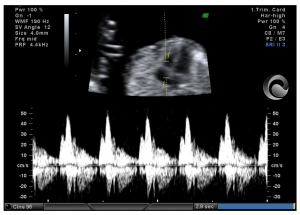

Correcta evaluación de flujo sanguíneo a través del ductus venoso fetal entre las 11-13 semanas